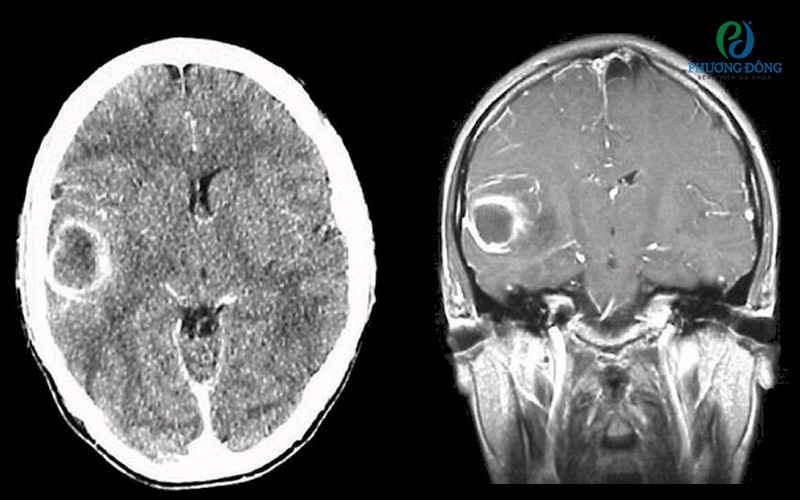

Hình ảnh áp xe não chụp CT cắt ngang có thuốc cản quang (trái) và ảnh chụp MRI T1 có thuốc cản quang gadolinium mặt phẳng đứng dọc (phải)Hình ảnh áp xe não chụp CT cắt ngang có thuốc cản quang (trái) và ảnh chụp MRI T1 có thuốc cản quang gadolinium mặt phẳng đứng dọc (phải)